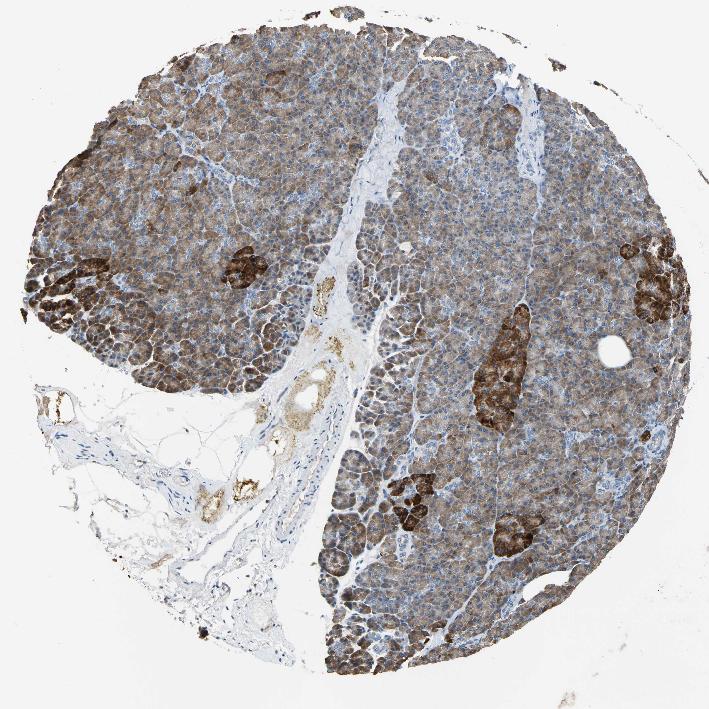

PANCREAS - Antibody stainingi

Antibody staining in the annotated cell types in the current human tissue is reported as not detected, low, medium, or high, based on conventional immunohistochemistry profiling in selected tissues. This score is based on the combination of the staining intensity and fraction of stained cells.

Each image is clickable and will lead to virtual microscopy that enables deeper exploration of all samples and also displays staining intensity scores, fraction scores and subcellular localization as well as patient and tissue information for each sample.

Antibody HPA005824

Exocrine glandular cells Medium

Pancreatic endocrine cells Low